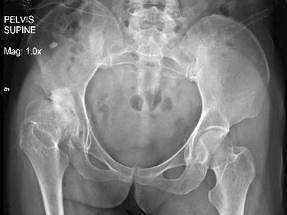

问题 右髋关节疼痛,跛行1年多,无明显外伤史,行双髋关节正位片如图示,最可能的诊断是 ( )

选项 A、右髋关节化脓性关节炎 B、右髋关节特发性骨关节病 C、右髋关节创伤性关节病 D、右髋关节结核 E、右髋关节退行性关节病

答案 E